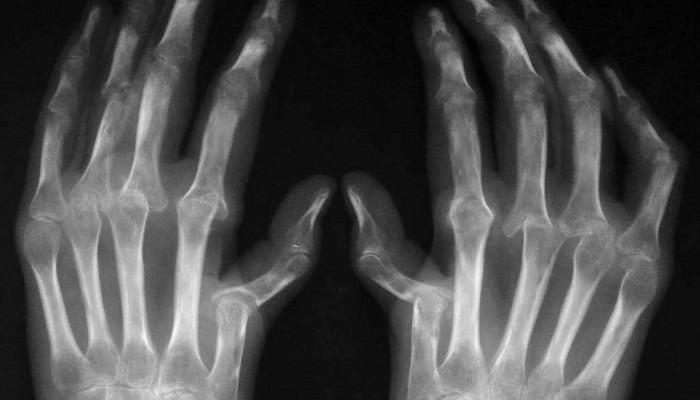

Рентгенография

Практически во всех случаях для постановки диагноза и анализа динамики болезни применяют рентгенографию. Околосуставной остеопороз – это один из первых рентгенологических симптомов раннего ревматоидного артрита. Также сужение суставной щели будет указывать на разрушение хрящевой ткани. По мере прогрессирования заболеванию начинают появляться костные эрозии (структурные нарушения). По их количеству и скорости возникновения новых дефектов можно определить характер течения артрита.

При запущенных формах наблюдается выраженные патологические изменения суставных поверхностей костей. Заключительная фаза болезни характеризуется развитием анкилозов (неподвижности суставов).